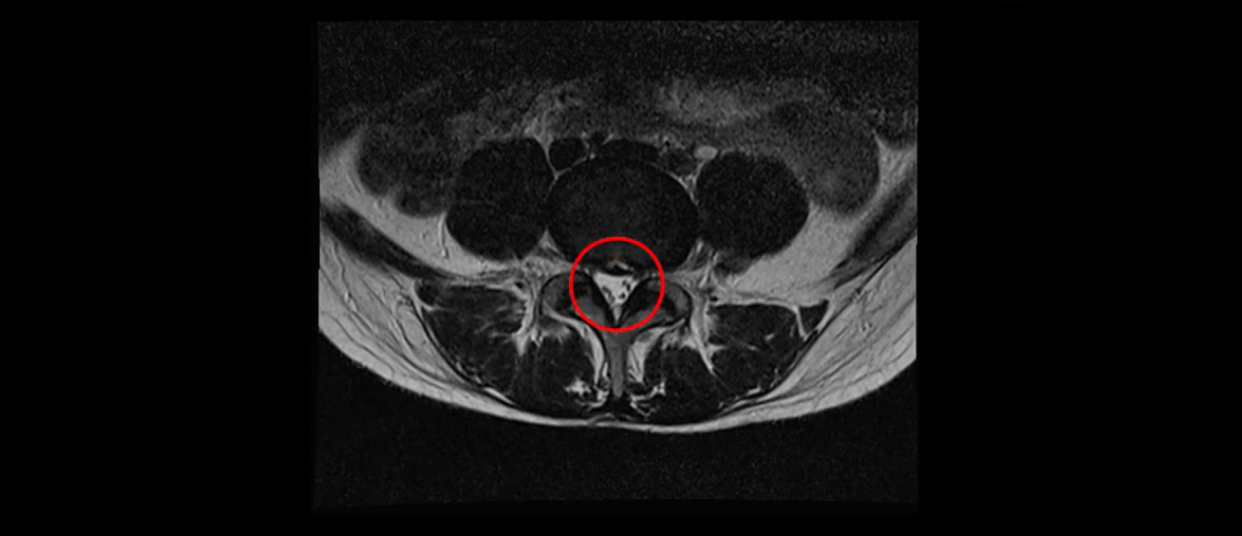

우선 이분의 MRI를 보고 먼저 설명을 드린 후 이런 환자분들의 통증의 원인은 무엇인지, 그리고 치료는 어떻게 해야 하는지 자세히 설명 드리겠습니다.

이분 MRI를 보시면 두 마디의 퇴행성디스크가 있습니다. 그리고 디스크가 조금씩 밀려 나와 있고요. 그런데 디스크 탈출 정도는 두 마디 다 심하지 않습니다. 4번 5번에는 디스크 탈출이 약간 있고,

척추관협착도 약간 진행이 되고 있고요.

5번 1번은 디스크 탈출이 가운데 쪽으로 살짝 있습니다.

또한 양쪽 신경 가지가 빠져나가는 추간공은 매우 넓은 상태입니다.

중요한 것은 이 정도 경미한 탈출과 협착으로는 양쪽 다리가 저리고 아플 수가 없습니다.

그리고 만약에 이 디스크가 급성으로 찢어진 것이라면 아주 심한 디스크성 통증이 있겠죠. 기침이나 재채기를 하면 심하게 아프고 허리를 조금만 구부려도 아주 날카로운 통증들이 생길 겁니다. 그런데 이분은 이런 증상이 전혀 아닙니다. 디스크의 돌출 정도와 협착이 전혀 심하지 않기 때문에 이분이 가지고 계신 양쪽 다리 저림, 특히 이분은 누워있을 때도 양쪽 다리가 저리다고 하는데, 디스크 때문에 그런 증상은 생길 수가 없습니다. 또 이 디스크는 오래된 디스크, 이미 찢어진 섬유륜이 아문 디스크이고, 그러니까 이분은 기침이나 재채기를 못하는 증상이 없는 거죠. 그 다음에 허리를 구부릴 때 뻐근한 증상은 있지만 아주 날카로운 통증은 없습니다.

이분 MRI를 보시면 퇴행성디스크가 있고 약간의 협착이 있지만 이 정도의 퇴행성디스크와 협착으로는 신경이 눌려서 양쪽 다리가 저리고 아픈 증상이 나올 수가 없습니다. 그래서 MRI와 이 환자분의 다리 증상이 매치가 안 된다고 하는 의사들이 많은 겁니다.